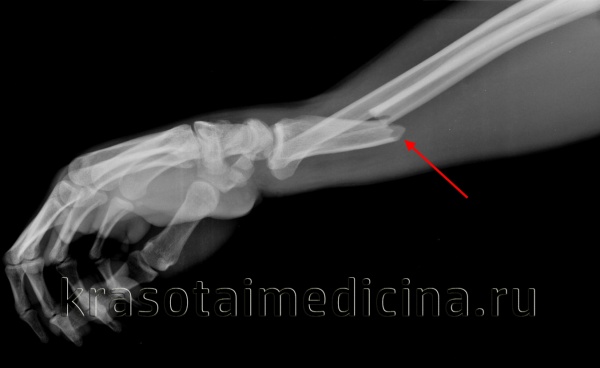

Внешний вид конечности после снятия гипсовой повязки. Рентгенограммы выполненные при помощи ЭОП на операционном столе выявили полное смещение всего дистального метафиза лучевой кости к тылу на целый поперечник.

Когда имеешь дело с таким переломом на фоне остеопороза становится ясно, что в метафизарной зоне будет «каша» из множества мелких отломков, и что суставная поверхность будет расколота минимум на 3 части.

Интраоперационно под контролем ЭОП произведена закрытая репозиция перелома.

После репозиции на рентгенограммах отчётливо виден многоооскольчатый, нестабильный характер перелома.